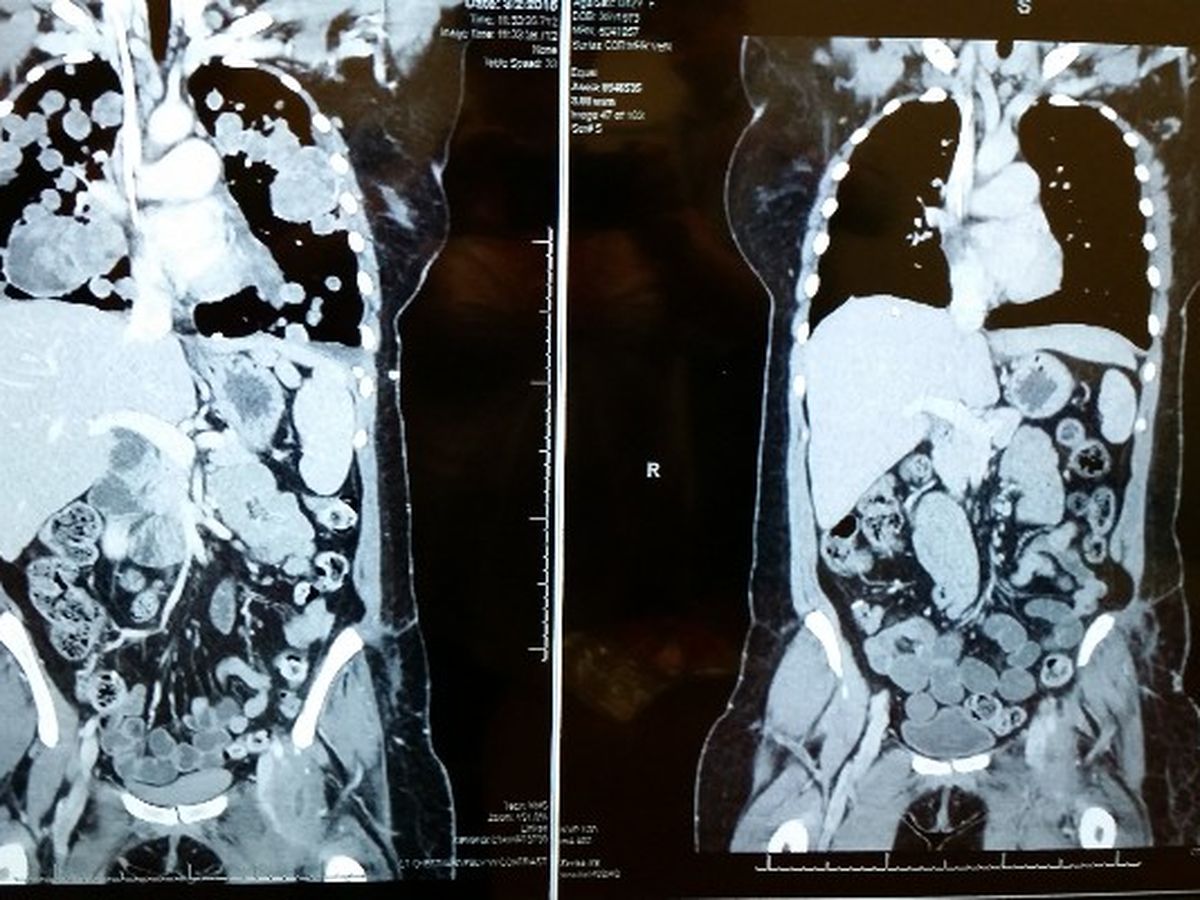

Now she is in the fight of her life. A fight for her life and she needs your help. Her path started on September 19th when she was diagnosed with Soft Tissue Sarcoma. The tumor was in the psoas muscle of her left leg. She received chemotherapy and was scheduled for radiation, but before that could happen it grew too fast and too large, so it was decided to remove it from her and within days she was off to surgery. The surgery was a success and the tumor removed. There were setbacks including a severe infection in the surgery site which extended her hospital stay to almost 3 weeks and delayed her next chemotherapy treatments. After a month of delays, we found out that her cancer had spread to her lungs and had grown so fast that her breathing was compromised. Her doctor decided to try another round of chemotherapy to try to shrink or slow the progression of the tumors in her lungs. It did not work. The cancer did not respond.

The way that this drug works, Nichol will have to be on it for the rest of her life in order to suppress her cancer. For this to happen she has to travel to Denver every 4 weeks for blood work and other tests such as CT scans. With the cost of airfare, food, and other expenses on top of the cost of her medical care it has put our already stretched budget under some serious strain.